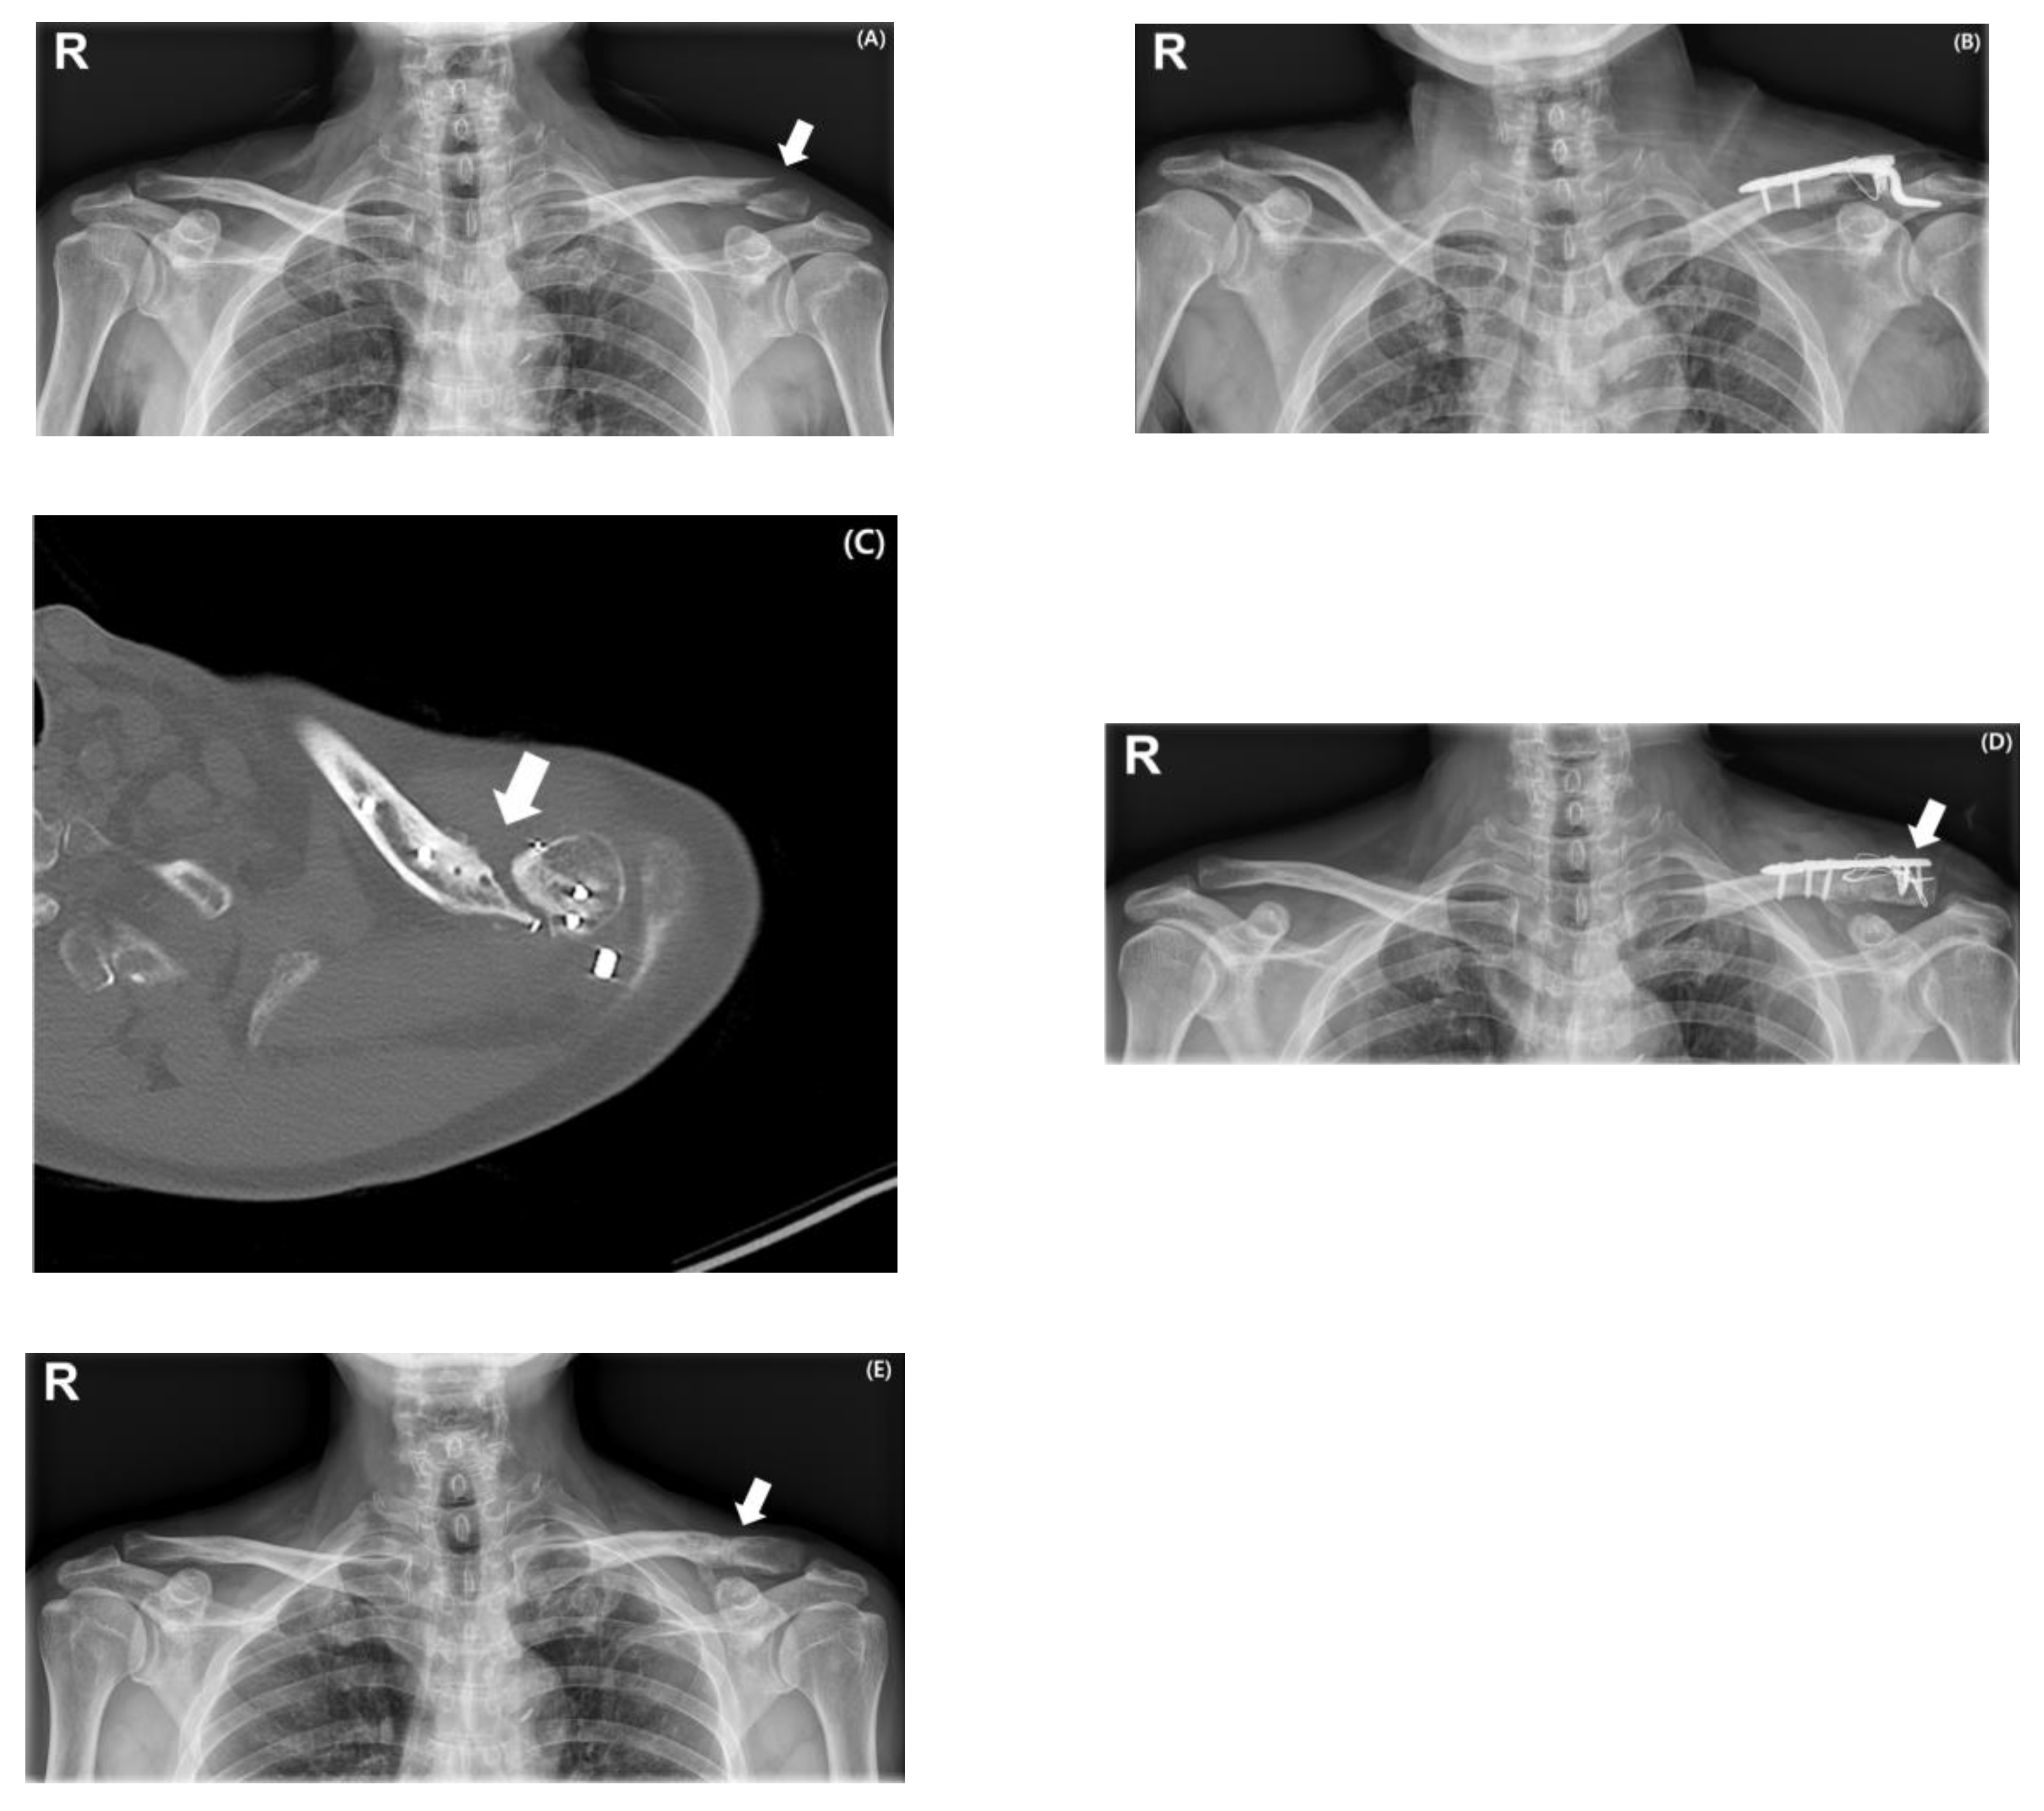

2.2. Surgical Procedures